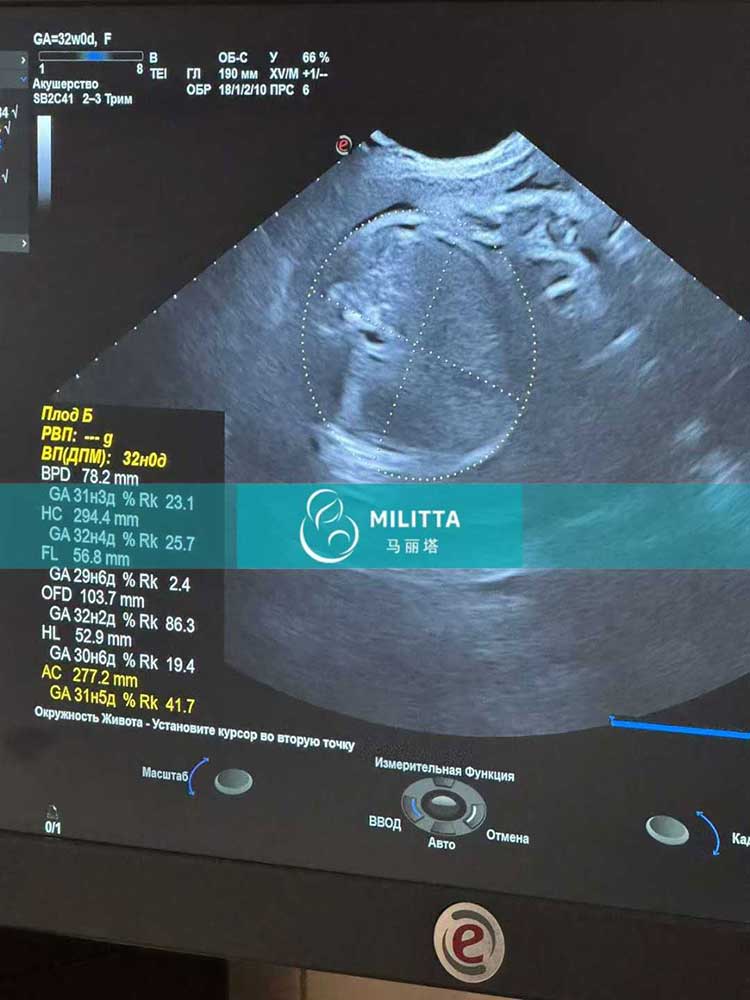

两位在乌克兰丽塔医院移植胚胎的试管妈妈在基辅做常规产检

两位在乌克兰LITA丽塔医院移植胚胎的试管妈妈在基辅做孕30周的常规产检,孕32周B超,检查胎儿状态都很好,感谢试管妈妈的照顾~